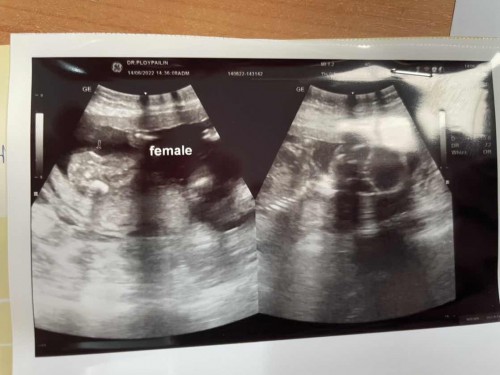

หมอบอกได้ลูกสาวค่ะ

ท้อง2แล้วอยากได้ลูกสาว คนโตผู้ชาย สมใจแม่มาก ตั้งใจจะปิดอู่ไม่ว่าจะชายหรือหญิง มีถามหมอกลับด้วย มีโอกาสที่จู๋จะยื่นออกมาไหม